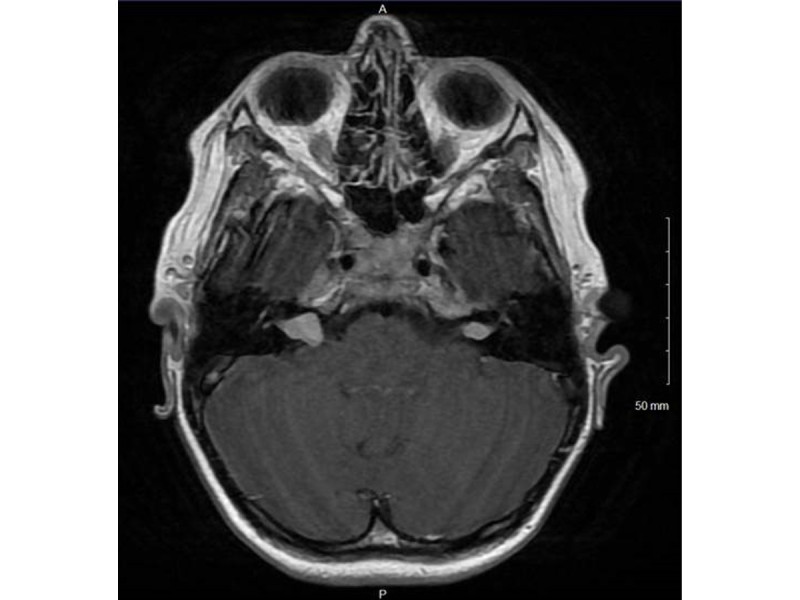

Oscar's scan

Just a bit of context, Oscar has bilateral VS (Vestibular Schwannoma), one of which grew 5mm in 1 year, C2 ependymoma which grew 7mm in 1 year and is turning cystic and a slight hearing loss.

(What is Avastin – see notes below)

Other NF2 related things – T2, L5, S1 schwannomas; parafalcine meningioma; small left cataract; foot drop; left sciatic nerve dysfunction; muscle atrophy – left leg

So our journey into this started in November 2022 when the latest scan showed growth in his Left VS and Ependymoma.